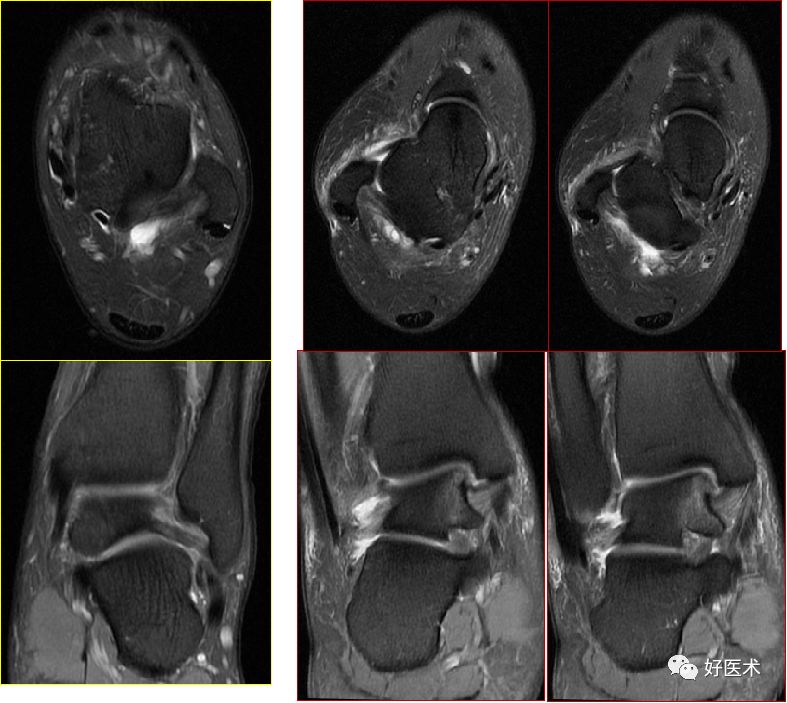

三、骨软骨病变

距骨骨软骨损伤,好发于前外侧、后内侧,尤其是后内侧,与内外翻损伤相关。

距骨骨软骨损伤分级

1度损伤:

2度损伤

3度损伤